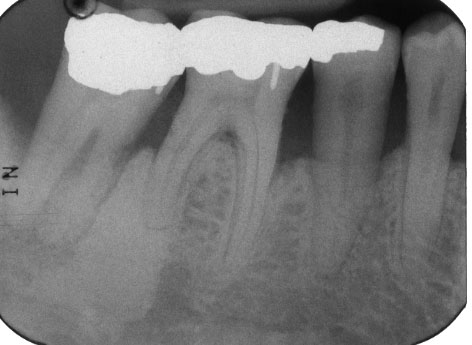

What is unique about this patient’s radiograph?

Bone is more radiopaque than normal. Probably has osteopetrosis.

What are these lesions caused by?

Osteopetrosis caused his bone to necrose, leading to these fistulous tracts.